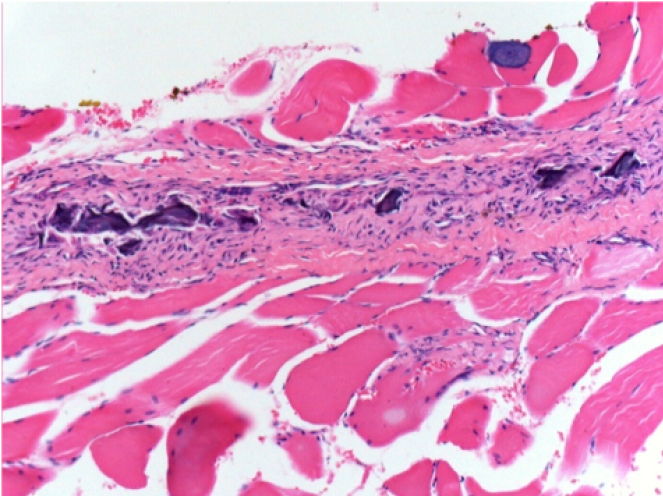

Через 10 днів після ін'єкції Ендопіл 0,1 мл в правий претибіальний м'яз.

Тут можна побачити утворення вакуолей, які оточені лімфоцитами. Вакуолі відрізняються від некрозу тканини. Присутність лімфоцитів пов'язана з проникністю клітинних мембран.